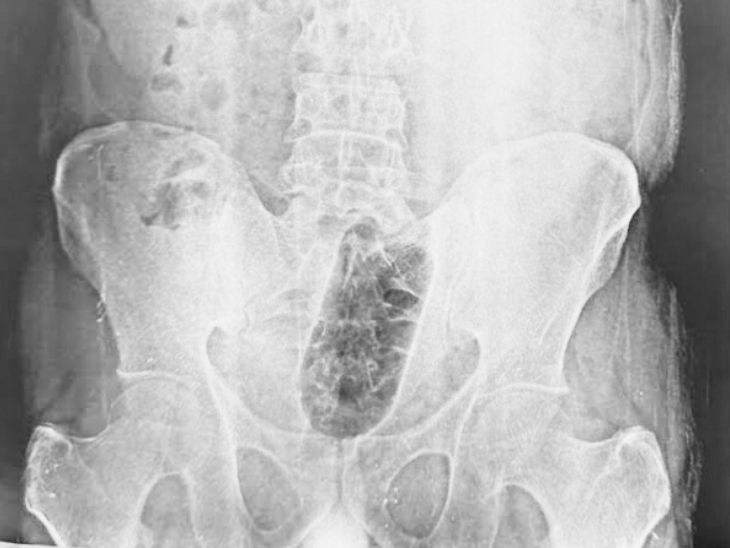

यहां डॉक्टरों ने युवक का एक्स-रे कराया तो मल द्वार के पास एक बोतल फंसी दिखाई दी। डॉक्टरों ने युवक को एडमिट करके इलाज शुरू किया। करीब एक घंटे के ऑपरेशन के बाद युवक को डिस्चार्ज किया गया। डॉक्टरों ने कहा-युवक साइको सेक्सुअल डिसआर्डर एनल एयरोटिसिस्म से पीड़ित है।

साकेत कालोनी में रहने वाला 38 साल के युवक शादीशुदा है। वह खुद का कारोबार करता है। युवक को असहनीय दर्द के चलते नवदीप हॉस्पिटल में मंगलवार को भर्ती कराया गया। डॉक्टरों ने तुरंत युवक का एक्सरे कराया। देखा कि मल द्वार के पास एक बोतल फंसी है।हास्पिटल के निदेशक वरिष्ठ सर्जन डॉ. सुनील शर्मा ने बताया कि युवक को तत्काल इमरजेंसी में भर्ती किया।